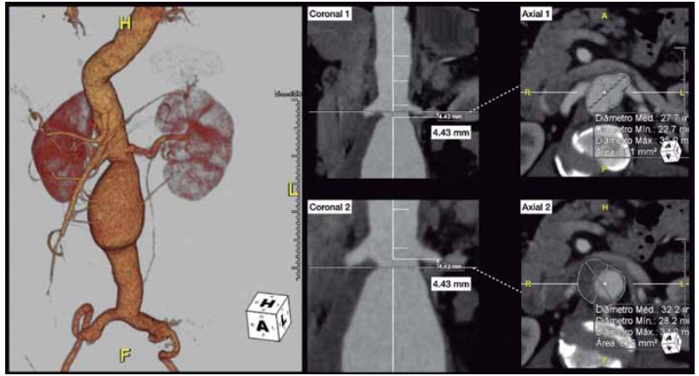

Alguns cortes tomográficos de interesse são apresentados na figura a seguir:

* As figuras Coronal 1 e Coronal 2 correspondem, respectivamente, ao mesmo plano indicado em Axial 1 e Axial 2 *